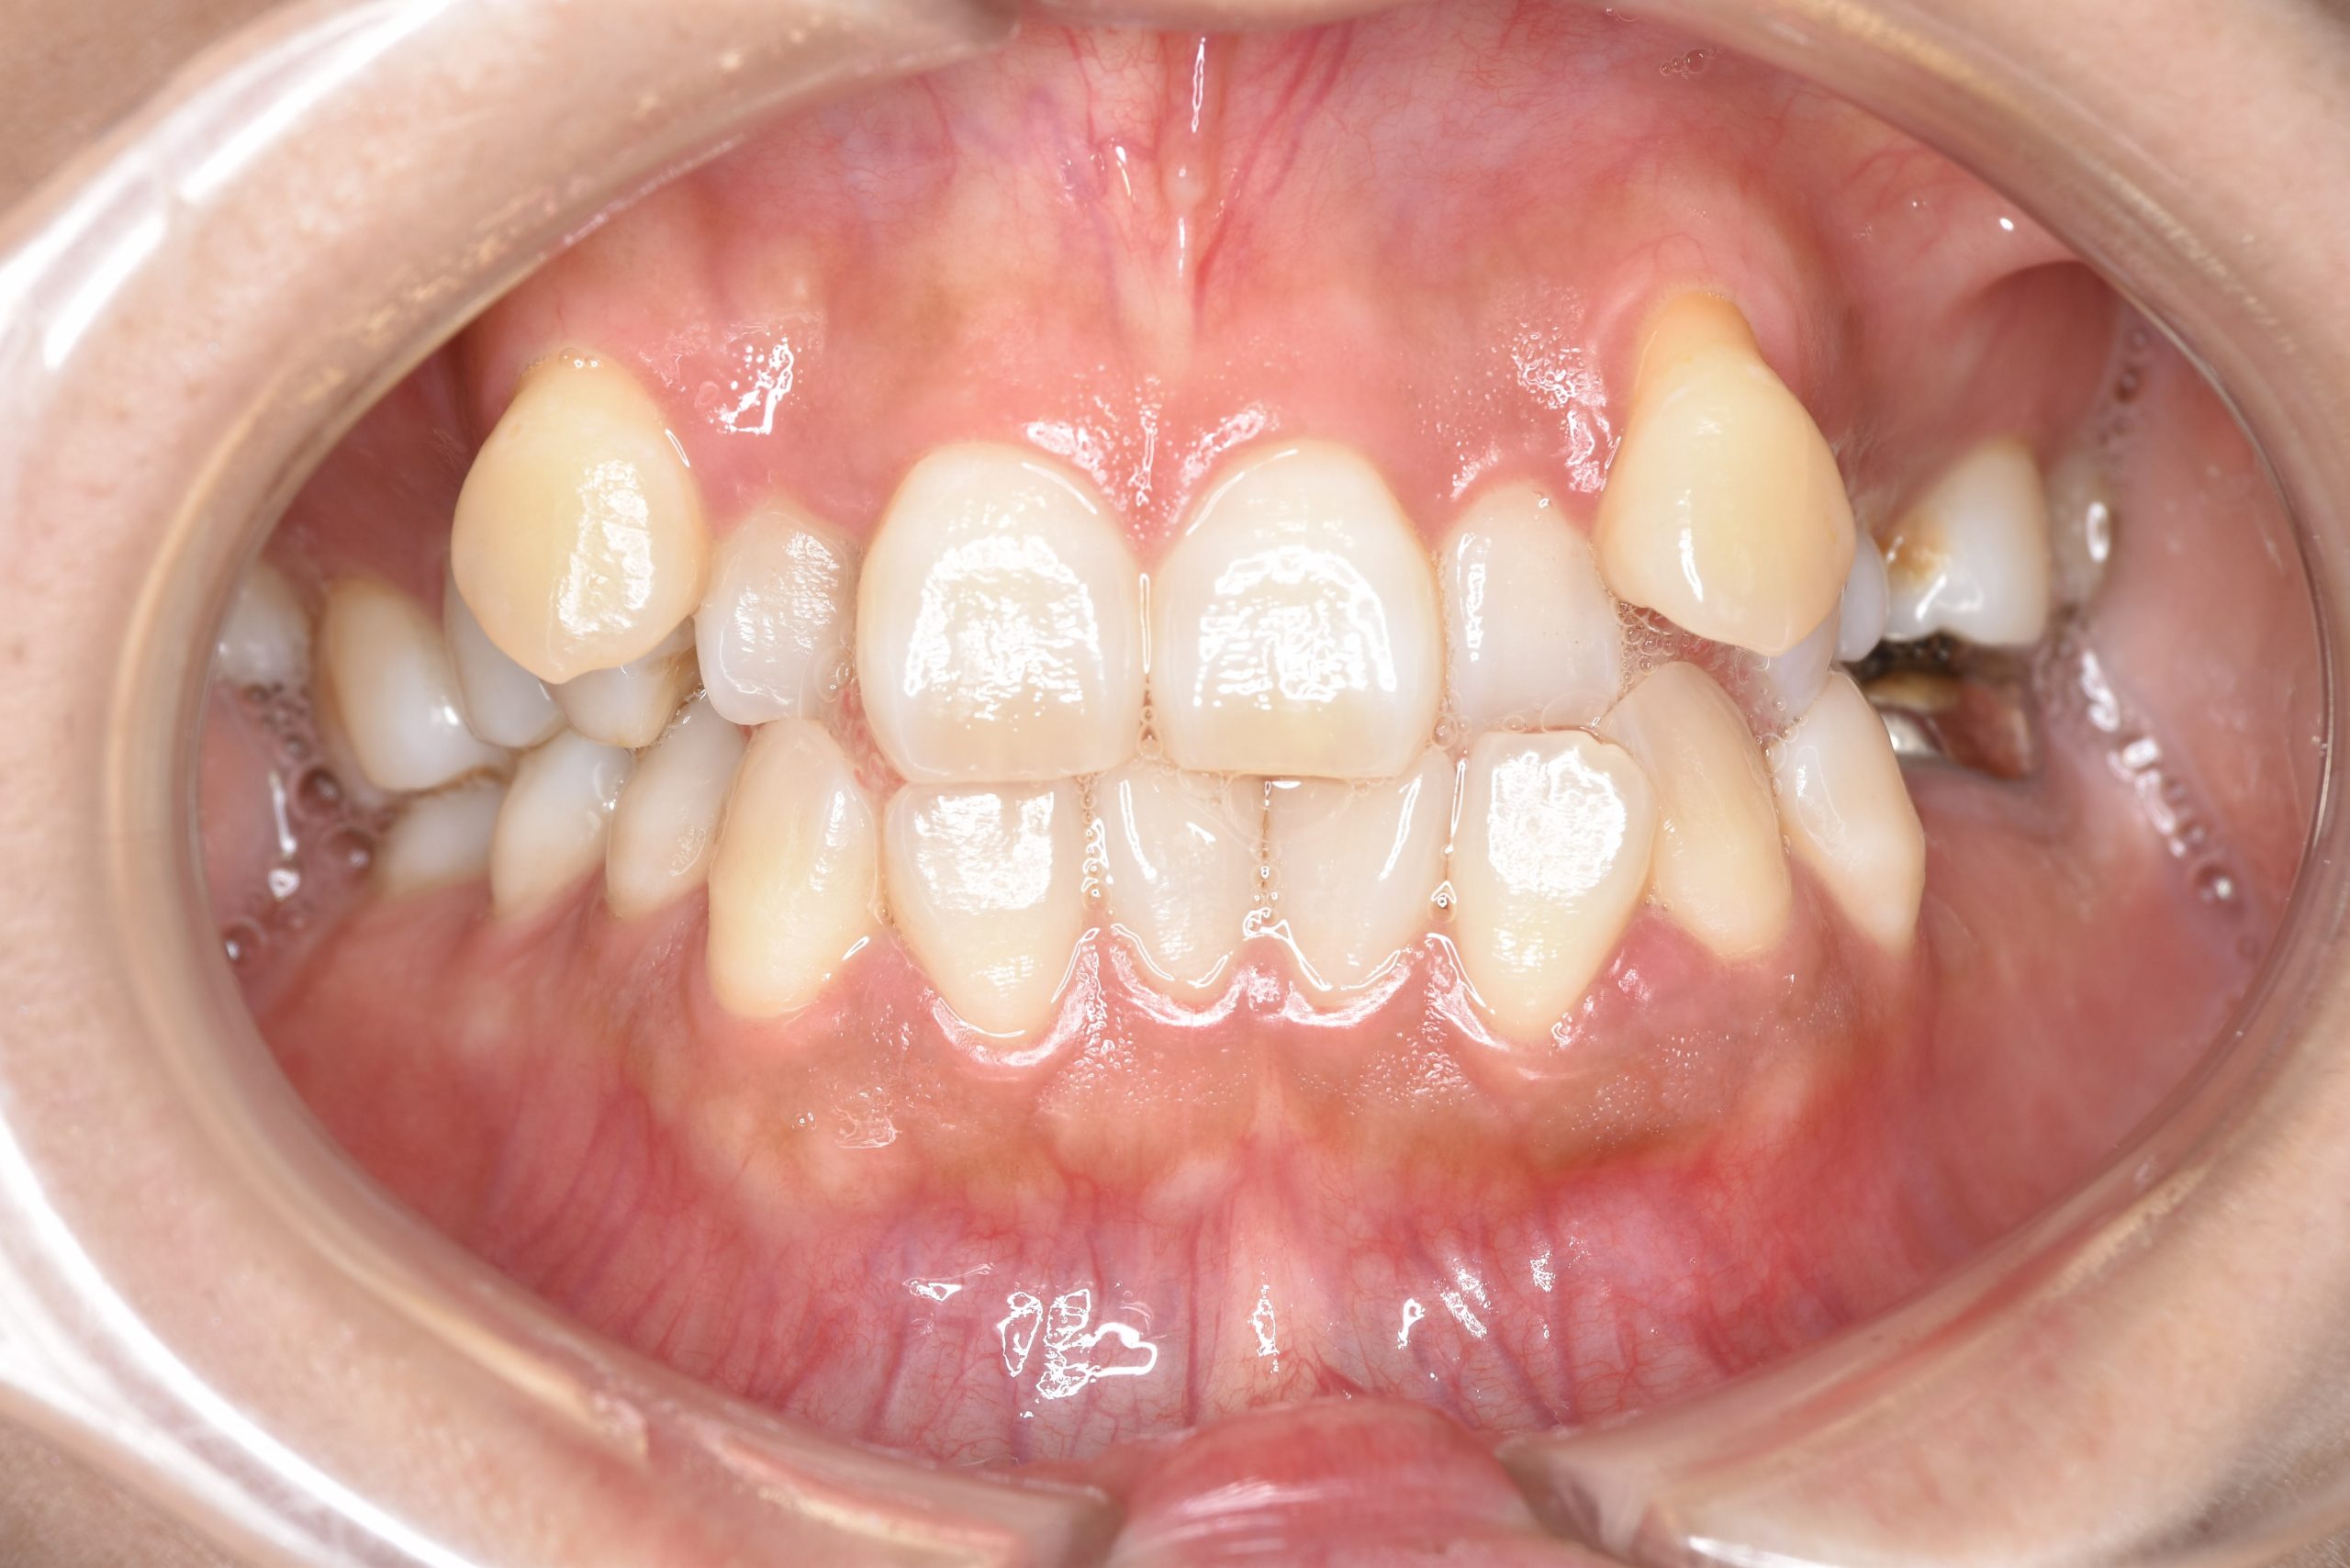

ビフォー

全顎ワイヤー矯正 症例_141

主訴 八重歯|上下センターがずれている

施術内容 成人矯正1期治療

治癒期間 4年10ヶ月間

費用 1,106,560円(税込)